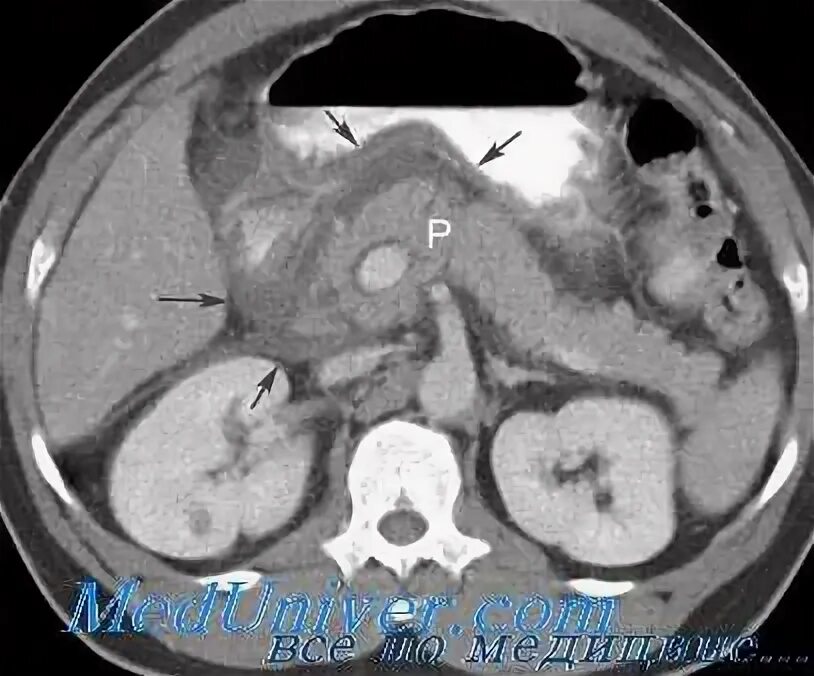

Пересадить поджелудочную железу